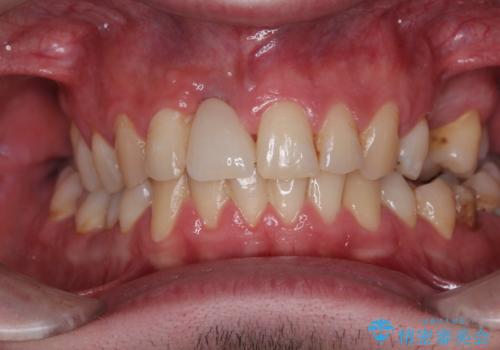

度重なる脱離により、表側の炎症が非常に強くなっており、歯を支える骨が失われている状態でした。

そのため、現在の位置よりも歯と歯肉の位置が退縮する方向に移動する可能性があり、前歯2本の歯肉位置が大きくずれることとなるため、本人との相談のうえ、天然歯が萌えているような歯肉状態とはならないものの、2本の段差が少ない状態にて治療を終えることとなりました。